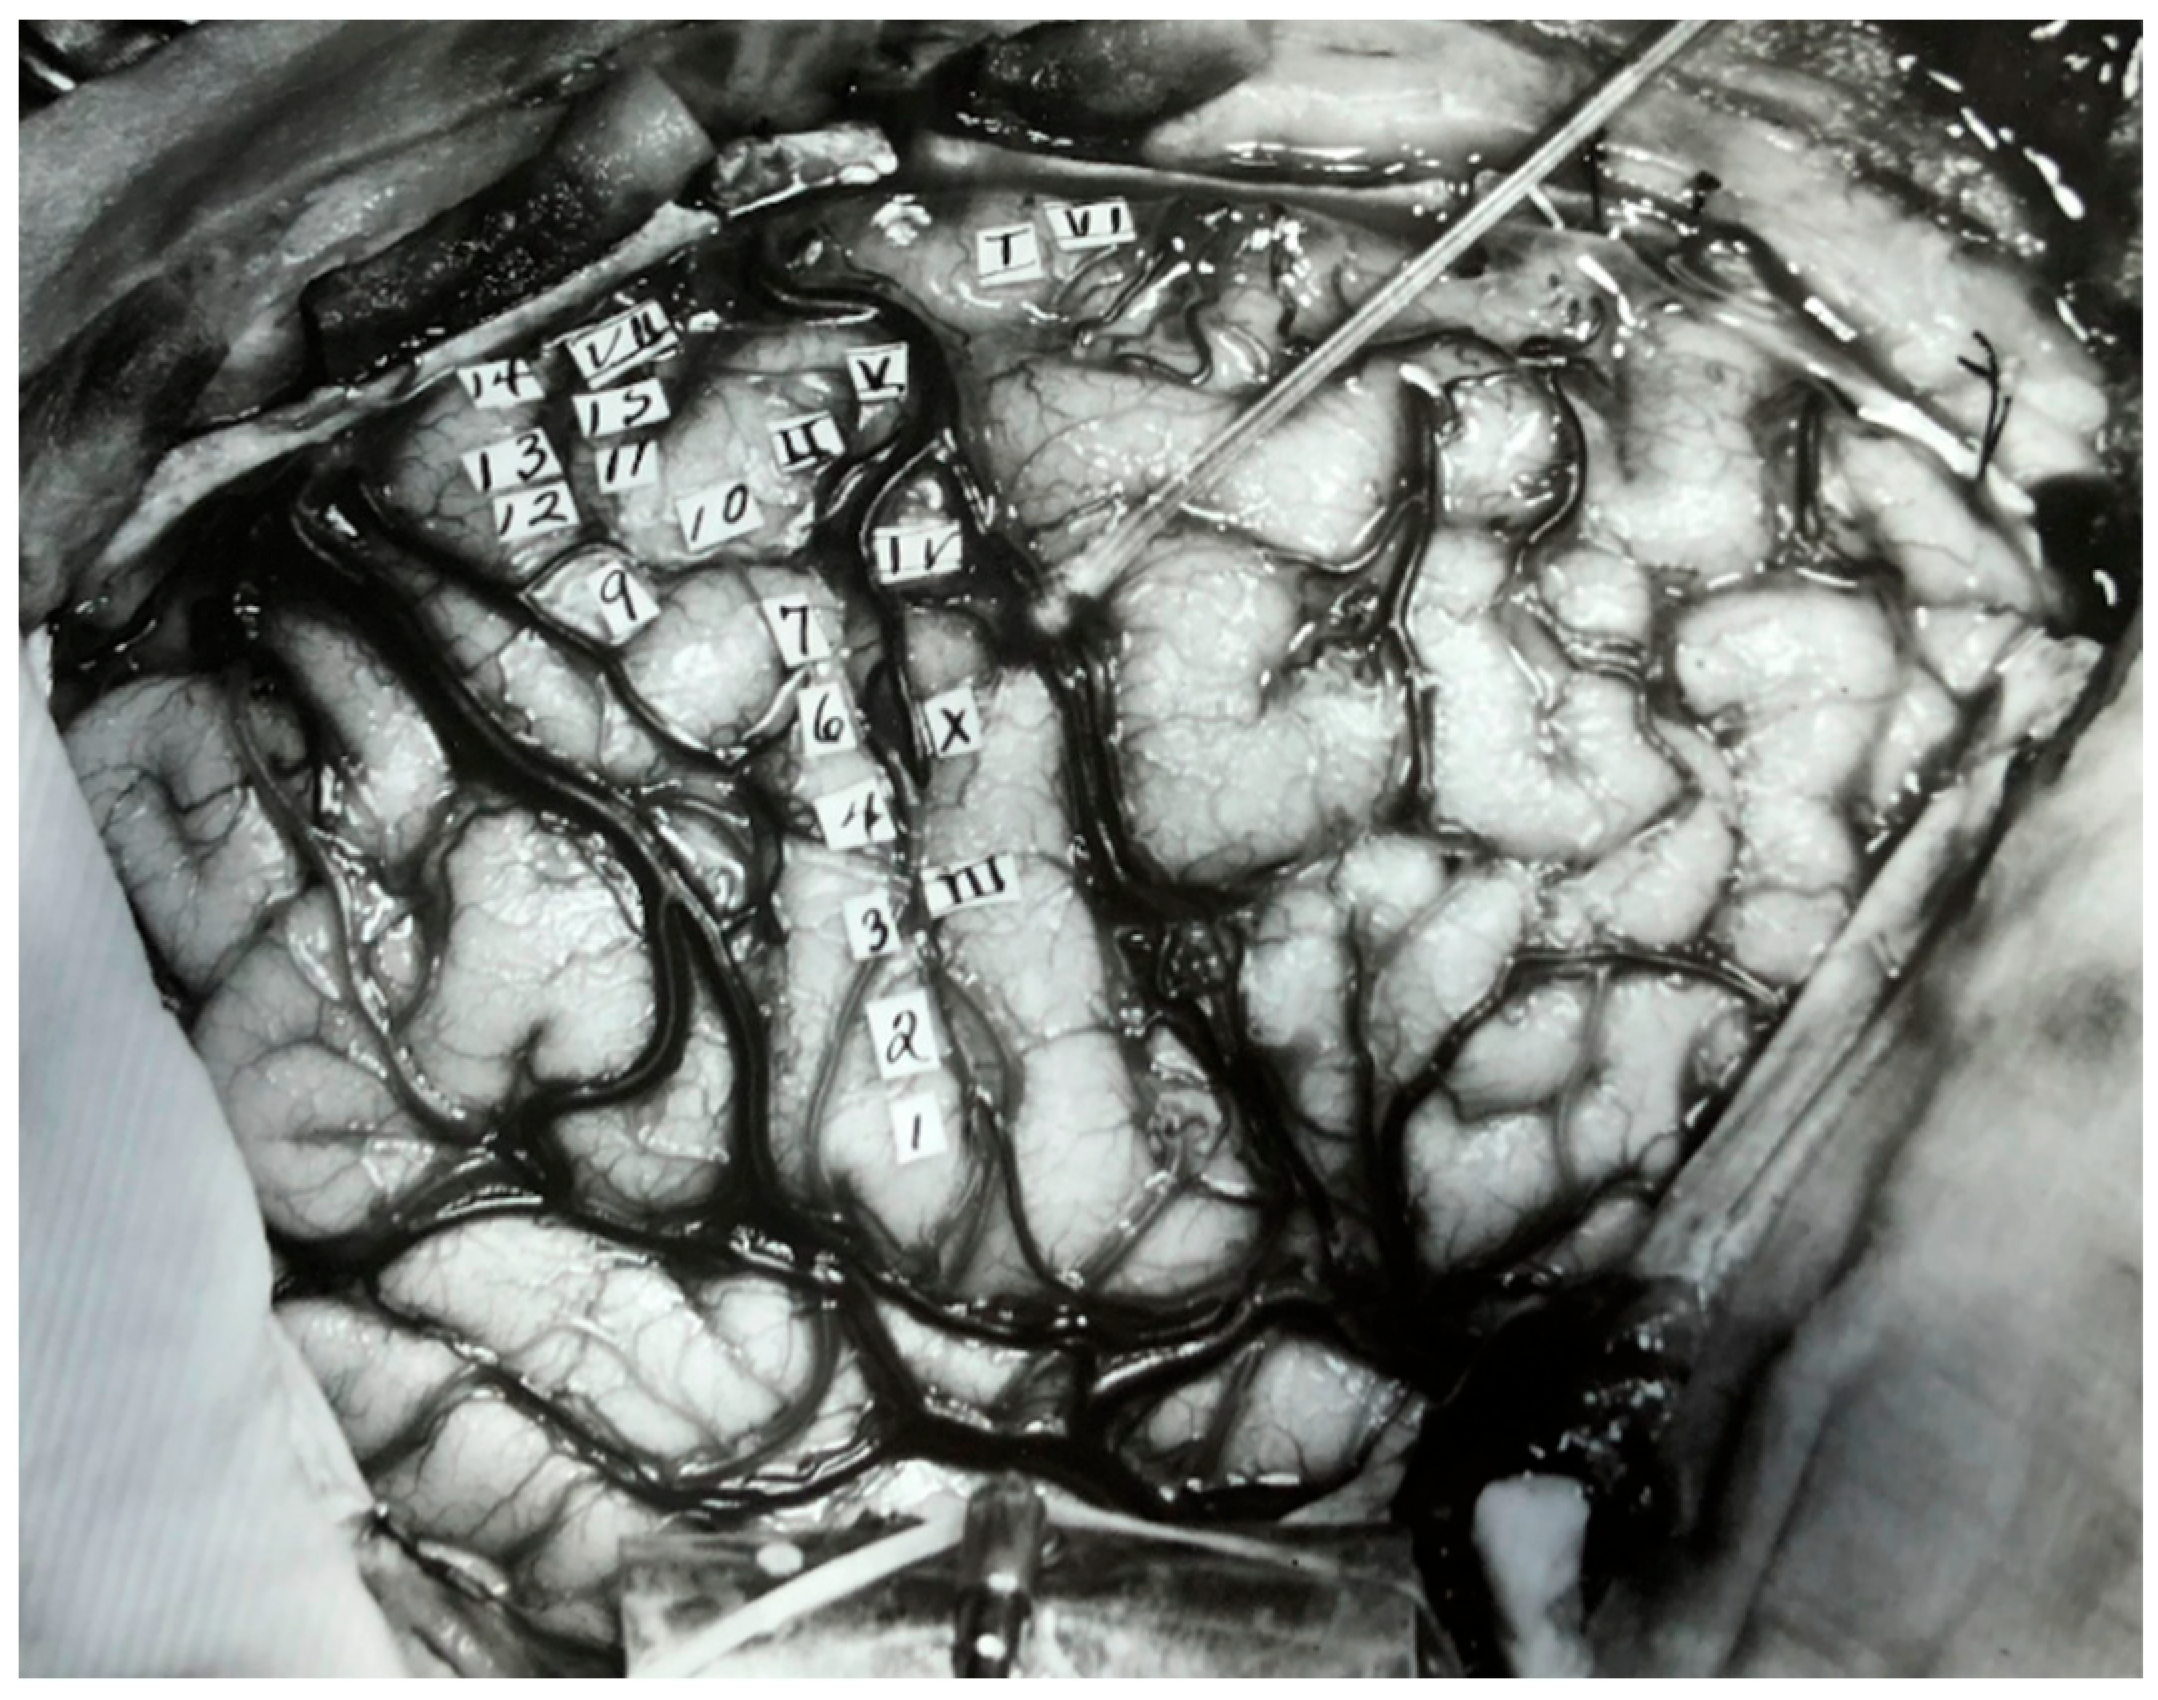

2. The Past